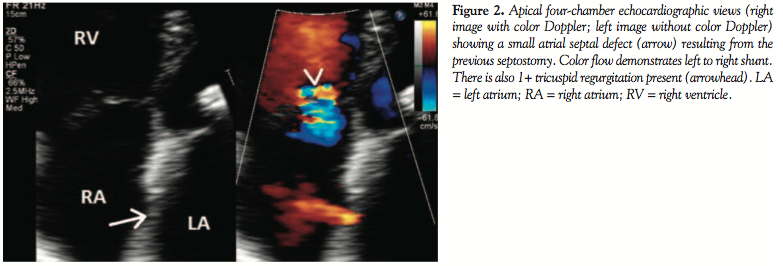

The patient underwent transthoracic echocardiographic and fluoroscopic-guided balloon valvuloplasty (Figure 1) using a standard transseptal technique and a 28 mm Inoue Balloon (Toray Industries). After valvuloplasty, the mean mitral gradient measured by simultaneous sampling in the left atrium and left ventricle was reduced from 9 mm Hg to 4 mm Hg, and the calculated valve area increased from 1.2 cm2 to 1.9 cm2. The mitral regurgitation by ventriculography remained unchanged (1+ before and after valvuloplasty). A shunt run at the end of the procedure showed a Qp/Qs of 1.2:1 (no shunt was present at the beginning of the procedure). The patient did well overnight following the procedure, and an echocardiogram the following morning showed a mean mitral valve gradient of 5 with a peak gradient of 9 and mild mitral regurgitation. Note was made at that time of “a small atrial septal defect” on both the apical 4-chamber and subcostal views with evidence of left-to-right shunting by color Doppler (Figure 2). The patient was subsequently discharged home. During routine clinical follow-up 1 month later, a review of systems revealed the patient was now experiencing migraine headaches that began a few days after her discharge. She had been seen by a neurologist, who prescribed abortive therapy to use as needed. She reported having 3-4 headaches a week that generally began with an aura of flashing lights and odd scents, followed by unilateral eye and left temporal throbbing. Brain magnetic resonance imaging scan and magnetic resonance angiogram were obtained and showed no stroke or vascular abnormalities. On further questioning, the patient revealed she had migraines as a child that caused her to frequently miss school, but had eventually grown out of them. A repeat echocardiogram was performed during her visit and showed a persistence of atrial level shunting. Color Doppler this time suggested bidirectional shunting and a bubble study confirmed right-to-left shunting.